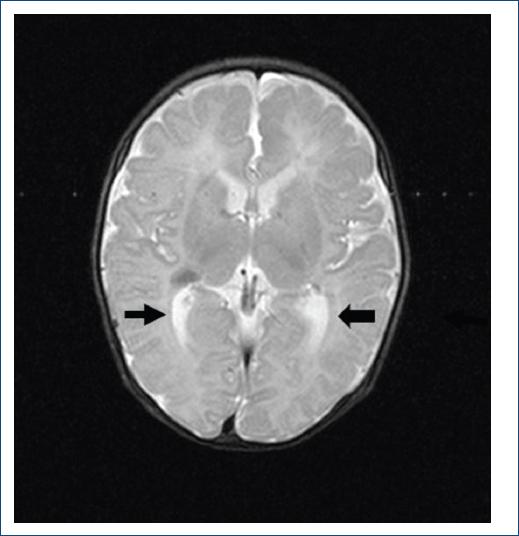

En 17 de ellos (71%) se hizo diagnóstico de ET, que se confirmó por imagen con TC y/o RM de encéfalo con presencia de calcificaciones interventriculares (Fig. 4).

Figura 4 Tomografía de cráneo corte transversal, donde se observan las tuberosidades intracraneanas, característico de la esclerosis tuberosa.

Se puede sospechar la presencia de ET con la tríada de Vogt: retraso mental, convulsiones y lesiones cutáneas. Existen criterios establecidos desde 1992 para su diagnóstico (Tabla 3). La RM aporta información adicional, ayudando a detectar lesiones tuberosas cerebrales asociadas a ET y a tumores extracardiacos10. Hay que tomar en cuenta que la ausencia de lesiones cerebrales o renales en la etapa prenatal no excluye la aparición posnatal4,14.